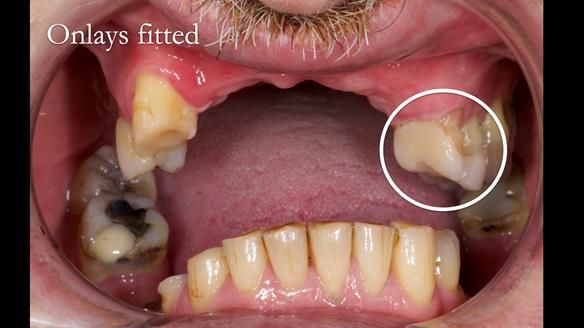

Keith’s case was one of the most challenging and rewarding cases I’ve treated this year. This 64 year old man presented with ill-fitting acrylic partial dentures that lacked stability, retention, and aesthetics. They constantly broke. He had lost the upper front teeth in a road traffic accident in his early 20s. The unopposed teeth had erupted, taking up space. After careful planning, we made a durable, metal-based upper partial denture/splint to address his dental concerns. He loved the outcome.

2. Onlay preparations: Composite onlays were fitted for his upper left premolars to repair these teeth and support the new denture.

Keith’s denture incorporated a Duracetal shell clasp on upper right first premolar (Myerson), which are designed to be virtually visible, providing a more aesthetic solution while enhancing patient comfort. The Scandinavian-inspired approach, based in modern removable prosthodontic techniques, ensured the denture was not only durable but also visually pleasing. Additionally, the design was carefully planned to allow for future modifications, ensuring that if Keith loses additional teeth, the denture can be adapted rather than replaced entirely.

I also used the Dahl concept to re-establish the occlusion upon fitting the RPD, which helped to intrude the lower left canine without needing to grind it too much.